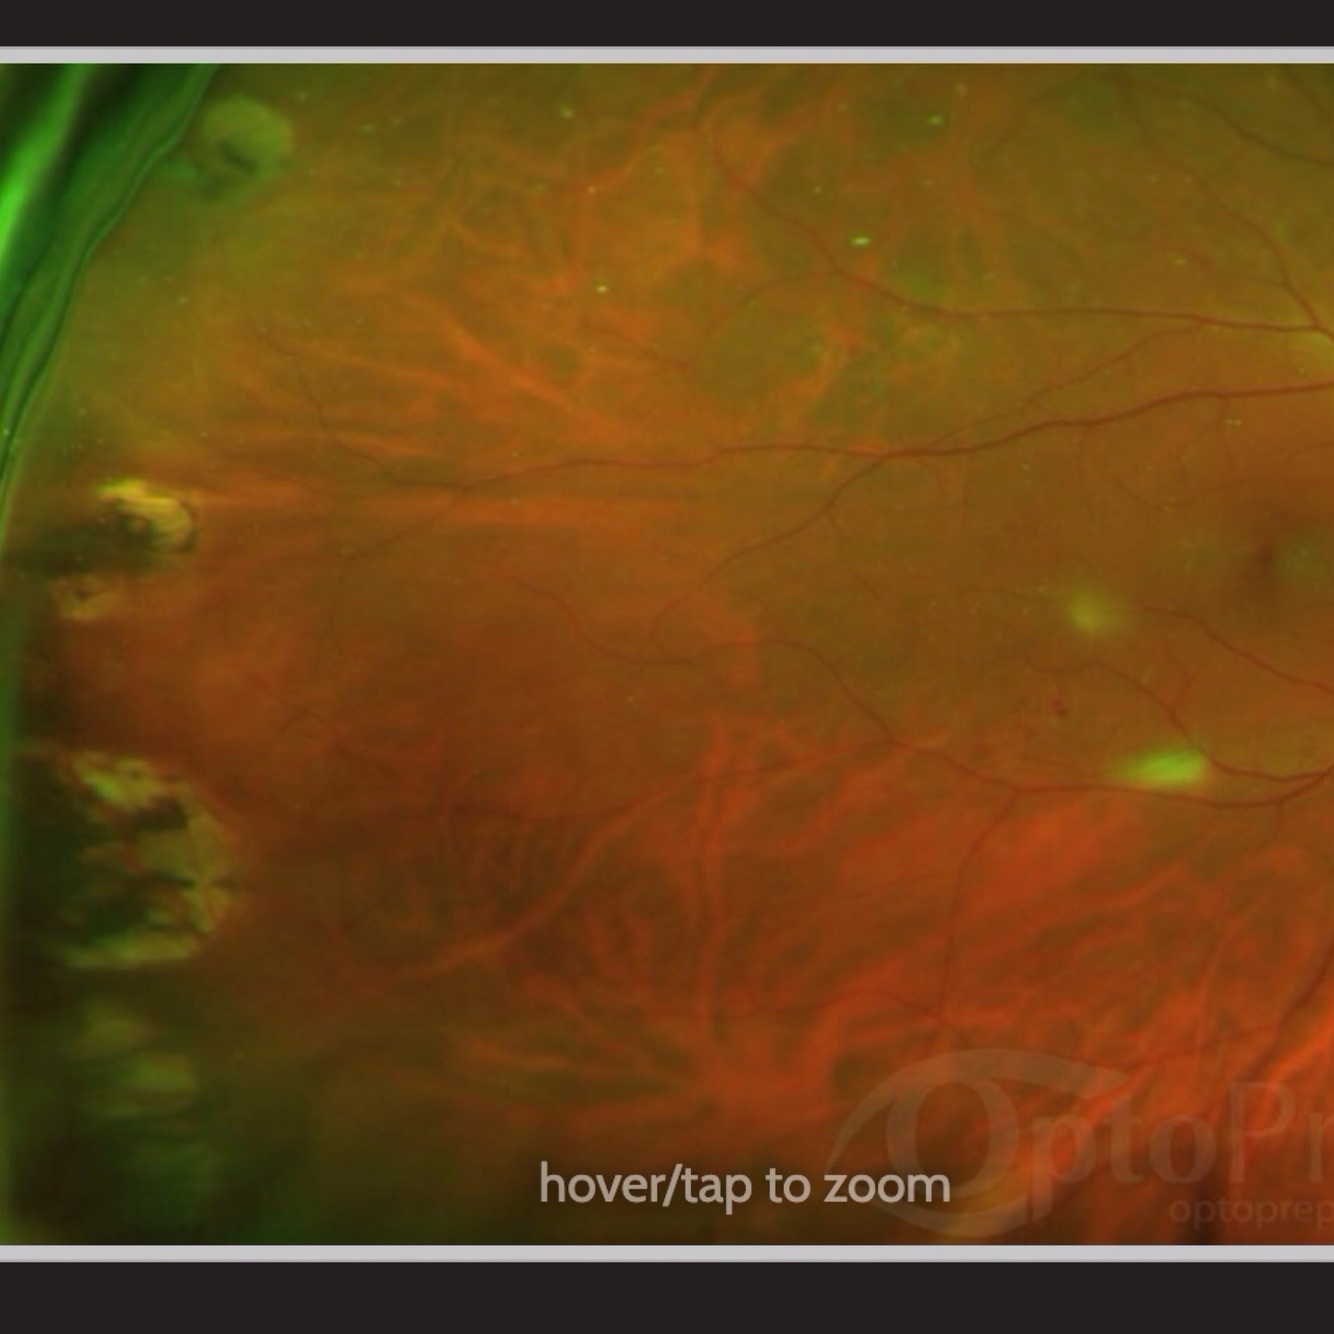

Retinal detachment * lesion is inferior nasal, patient will report phototopsias superior temporally

Retinal detachment